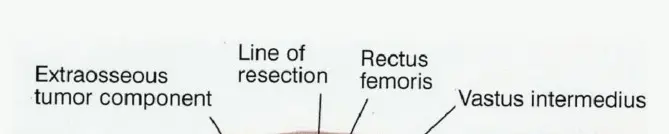

الشكل 1: أ. صورة أشعة سينية تظهر ورمًا نقيليًا في الحُق الأيمن لدى رجل يبلغ من العمر 72 عامًا ولديه تاريخ معروف بسرطان الغدة الدرقية. ب. يظهر التصوير المقطعي المحوسب (CT) تدميرًا واسعًا للعظام وامتدادًا للأنسجة الرخوة. محاولة الاستئصال بناءً على النتائج الشعاعية وحدها قد تؤدي إلى استئصال جزئي للآفة ونزيف محتمل بسبب الأوعية الدموية الكثيفة لهذا الورم. بالنظر إلى هذه النتائج الشعاعية، خضع هذا المريض لانسداد وعائي قبل الجراحة مما قلل من فقدان الدم أثناء الجراحة وسمح باستئصال ناجح.